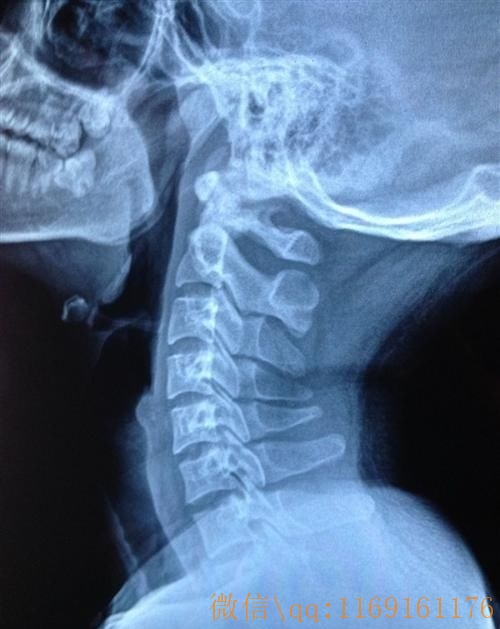

颈椎病的主要物理检查方法有哪些?

颈椎病的主要物理检查方法如下:

(2)颈椎活动范围检查。可以通过颈部前屈、后伸、旋转与侧屈活动,用量角器测量后,根据正常活动范围,判断是否有活动受限。一般神经根型、颈型颈椎病患者的颈椎屈伸和旋转活动易受限。